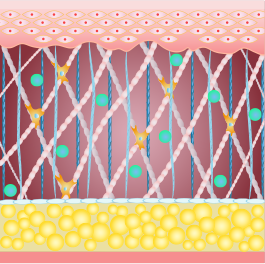

콜라겐 구조의 70%

클로인,프롤린,라이신은 콜라겐의 70%를 차지합니다.

섬유아세포가 대사활동을 하는 동안 섬유아세포에 자극을 주어

콜라겐을 생성하거나, 콜라겐이 서로 합성되는 현상이 일어납니다.